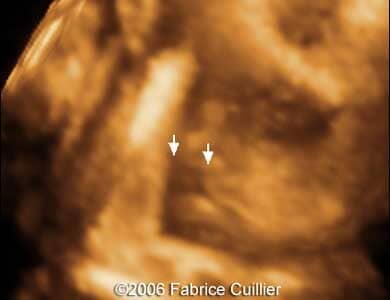

Pictures 5, 6. 3D pictures showing unilateral cleft lip.

Pictures 7, 8. 3D pictures showing unilateral cleft lip.